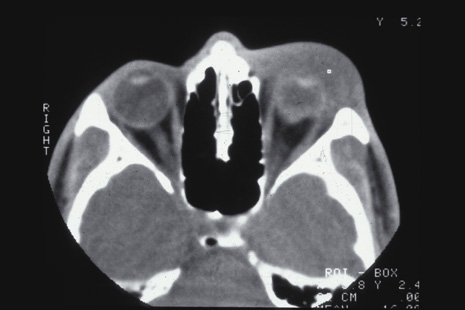

SCLERAL RUPTURE In eyes that have not undergone prior surgery, the two most common locations for scleral rupture are at the limbus (under intact conjunctiva) and parallel to the muscle insertions between the insertion and the equator. Radial and posterior ruptures are relatively uncommon.29 The hallmarks of scleral rupture are severe reduction in visual acuity, an afferent pupillary defect, hypotony (although a normal intraocular pressure does not rule out a small rupture), an abnormally deep anterior chamber, decreased ocular ductions, severe subconjunctival edema (Fig. 24), hyphema, and vitreous hemorrhage.92 The diagnosis can rarely be confirmed by ophthalmoscopy because severe vitreous hemorrhage, hyphema, or both nearly always accompany scleral rupture. Ultrasonography and computed tomography (CT) scanning may be helpful. Both show a shrunken globe. In addition, the CT scan shows subconjunctival edema (Fig. 25). In eyes in which the anterior chamber depth cannot be seen because hyphema, ultrasonography and CT scanning often show a deepened chamber. CT scanning is also useful in identifying any intraocular foreign bodies.